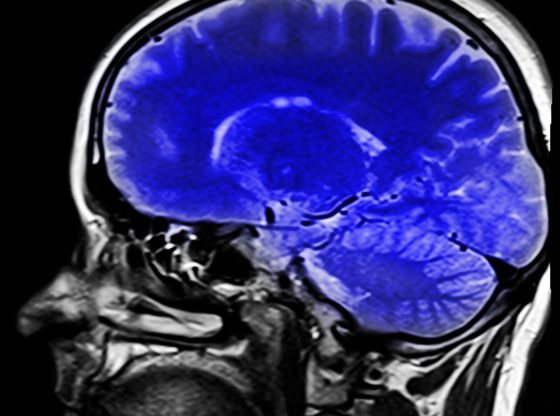

Rezonans Magnetyczny (RM) to zaawansowana technika obrazowania, która odgrywa kluczową rolę w dziedzinie medycyny. Od swojego odkrycia w latach 70. XX wieku, rezonans magnetyczny stale…